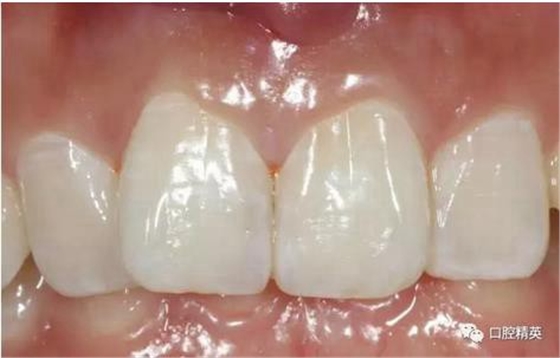

術(shù)前檢查

可見(jiàn)兩側(cè)齦緣外形不平整

口內(nèi)正側(cè)位及切端特寫(xiě)